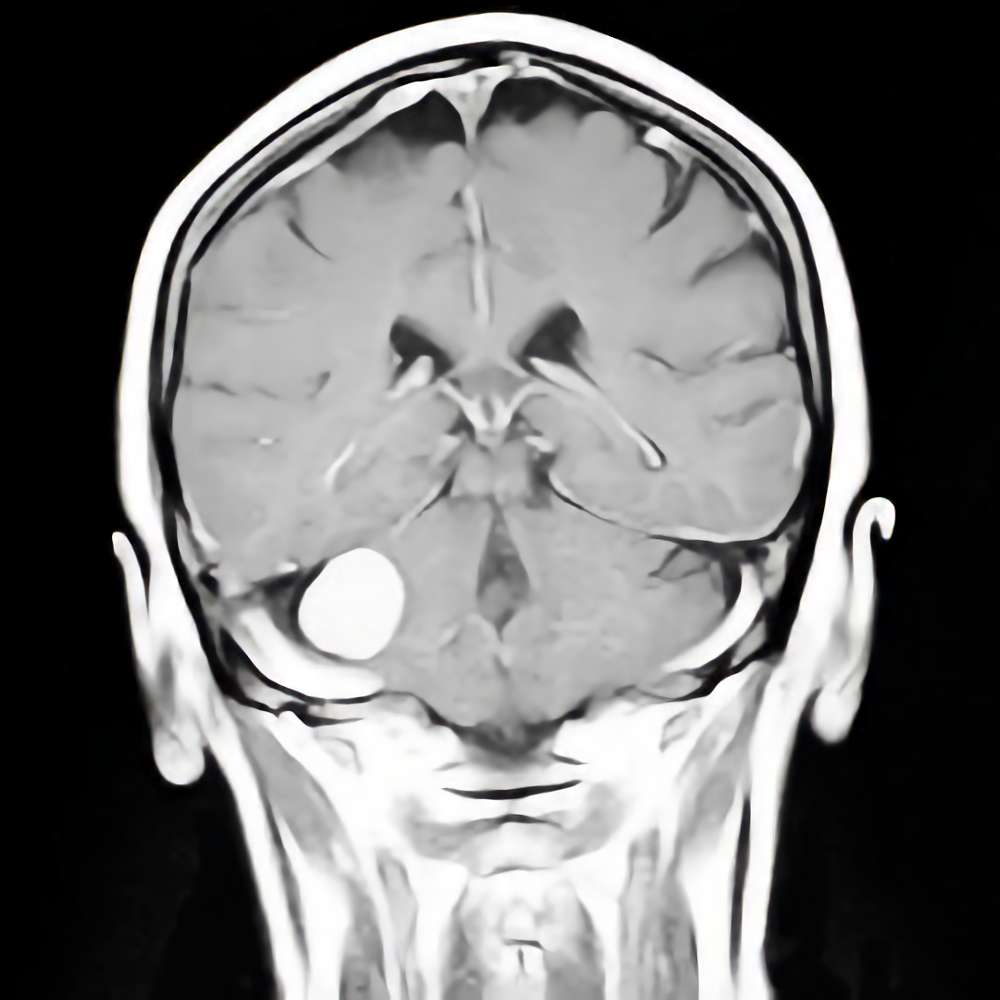

218

'21年9月

80代

左後頭頂葉腫瘤

頭蓋内腫瘍摘出術